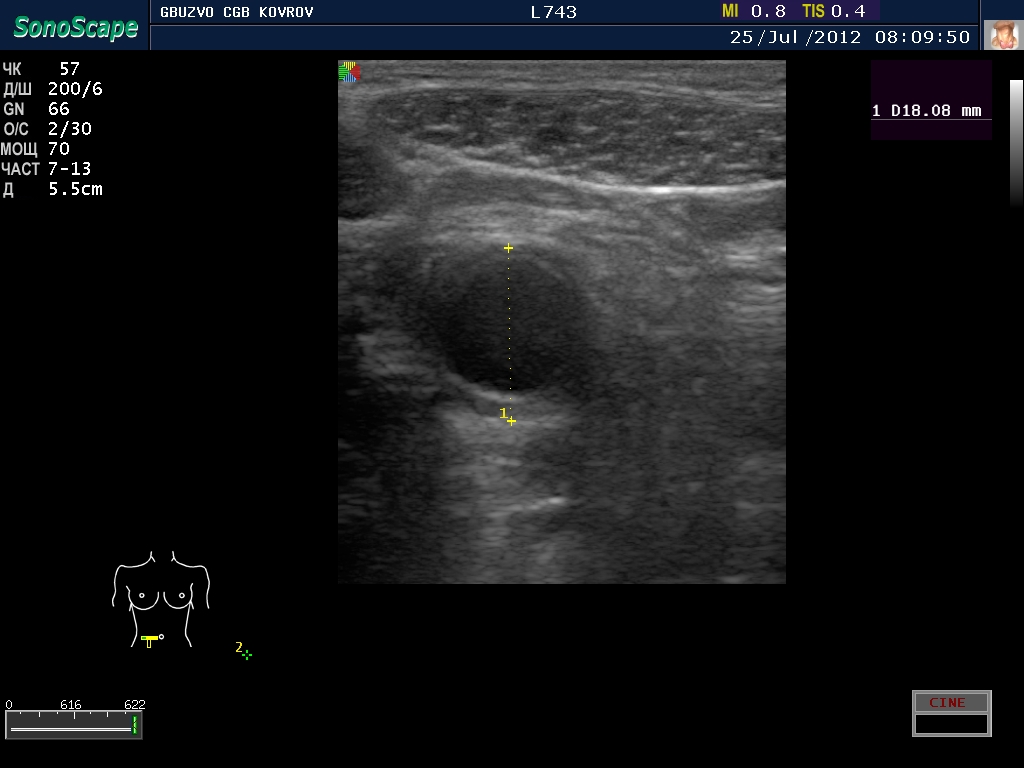

Пациент с жалобами на боли в животе...

jul252012081644.jpg

jul252012081644.jpg [ 202.73 KiB | Просмотров: 23706 ]

Что это такое? Кишка?

ну, скажем так, часть кишечника :D

поподробнее? :shock: бодимаркер находится в правой подвсздошной области, я бы подумал про аппендикс 8-)